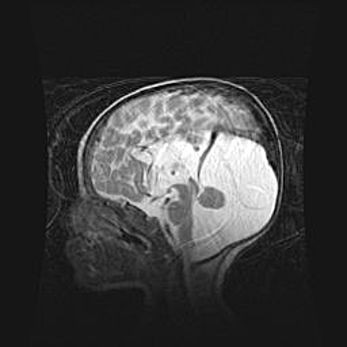

Лейкомаляция с кистозно-глиозной дегенерацией головного мозга.

Возраст: 2 месяца 25 дней

Вес: 6400 г

Окружность головы: 40 см

Срок гестации: 41 неделя

Лейкомаляцию относят к ишемически-гипоксическим повреждениям головного мозга, диагностируемым у новорожденных. При лейкомаляции в головном мозге обнаруживают очаги некроза, возникшие после тяжелой гипоксии и нарушения кровотока. В процессе морфогенеза очаги проходят три стадии: 1) развития некроза, 2) резорбции и 3) формирования глиозного рубца или кисты. Перивентрикулярная лейкомаляция (ПЛ) встречается примерно в 12% случаев среди новорожденных, обычно – у недоношенных детей, причем, частота ее зависит от массы, с которой младенец появился на свет. Наибольшее число малышей страдает лейкомаляцией, если масса при рождении 1500-2500 г.